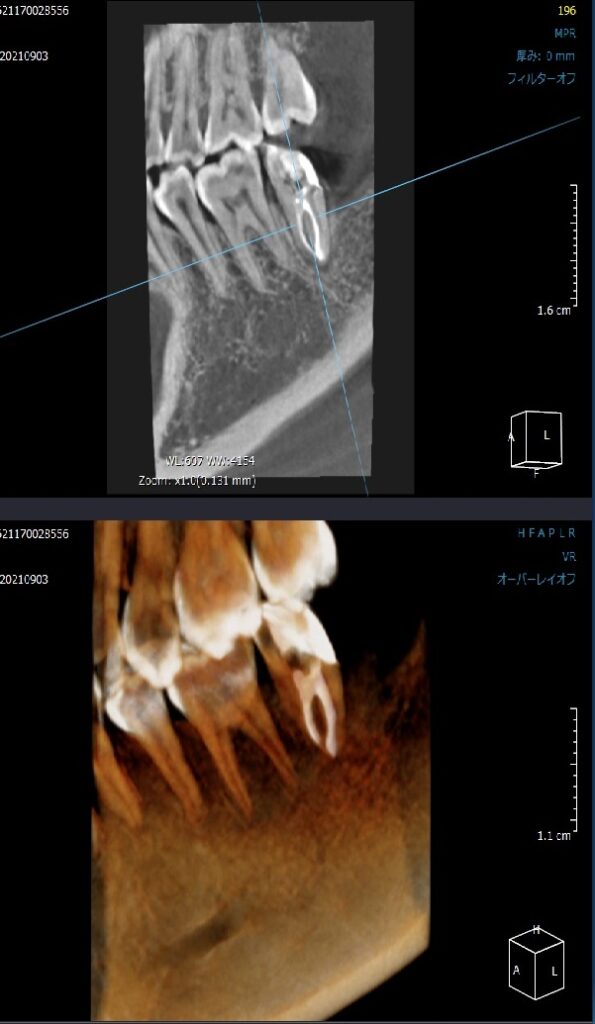

根管治療が終了したCT画像です。

3次元的に確認します。

根の中に白く写っているのがお薬です。

2つの根管が根の先で1つになっているのも分かります。